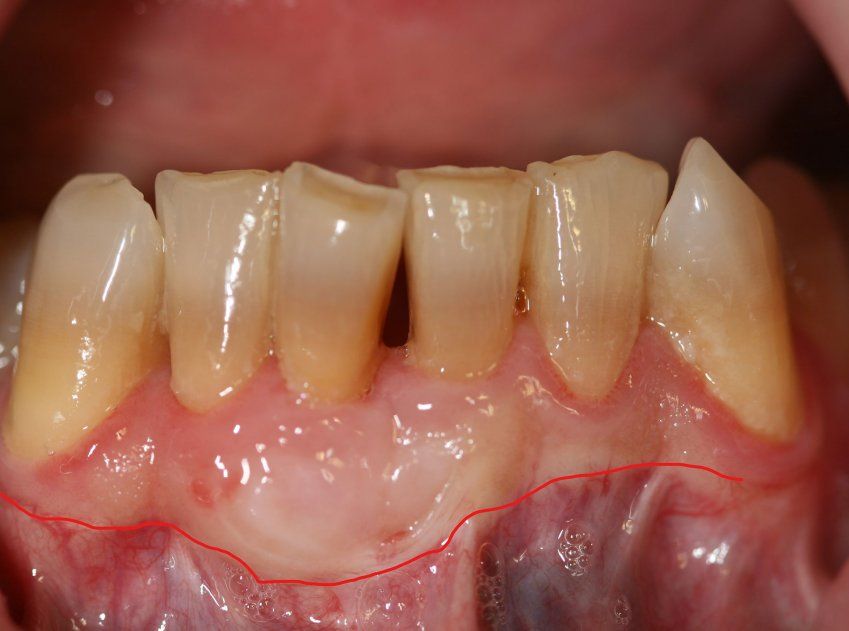

Es el tratamiento indicado cuando hay piedras o sarro subgingival, es decir, cuando hay sarro acumulado que se encuentra por debajo de la encía, generando una especie de sobre (bolsa periodontal) llena de microorganismos muy patógenos que degradan el hueso y afectan a los tejidos de soporte del diente (con la consiguiente aparición de la enfermedad periodontal o piorrea).

El tratamiento consiste en utilizar un ultrasonido para despegar el sarro o piedra acumulada y luego con curetas se alisan las superficies para dejarlas pulidas y que la piedra no se adhiera fácilmente de nuevo.